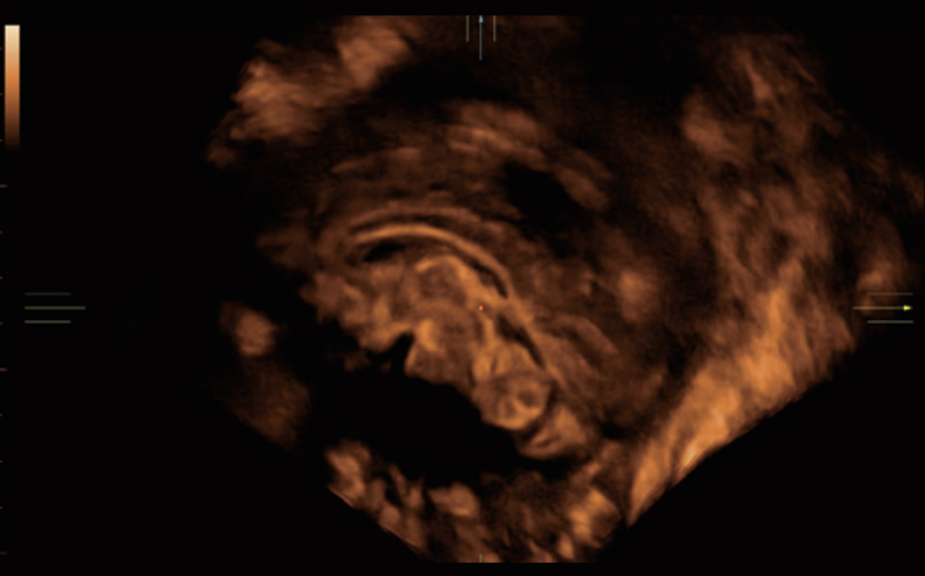

Obrazy kliniczne